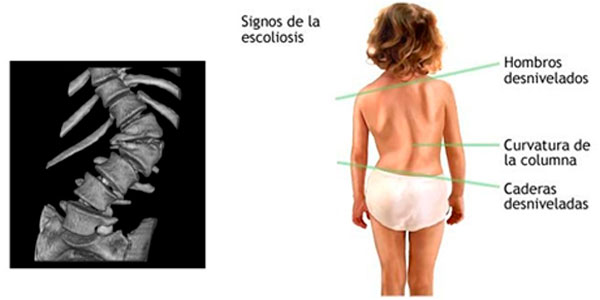

Actualmente es posible en algunos casos durante los controles ecograficos en mujeres embarazadas se pueda detectar algunas alteraciones en la estructura de la columna y detectar una escoliosis de manera muy precoz.

Sin embargo esto solo se puede confirmarse cuando el bebe nace y ver la evolución con el crecimiento del niño.

En algunos casos, las escoliosis congenita solo se hace evidente en la pubertad o adolescencia y otros cuando comienzan a caminar.

Al tener un diagnostico de escoliosis congenita debe descartarse otras malformaciones en otros organos y/o sistemas:

Es necesario evaluar con detalle al niño y solicitar estudios de imágenes que nos puede mostrar la estructura de la columna en forma completa.